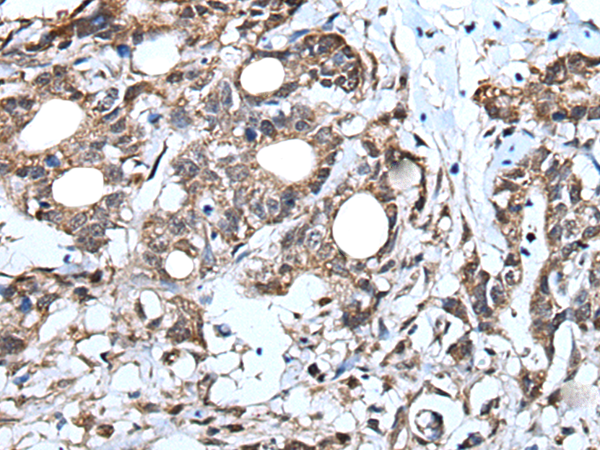

IHC positive control: |

Human brain and human lung cancer |

IHC Recommend dilution: |

30-150 |